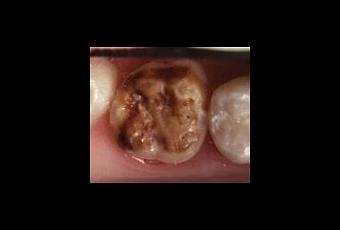

Le MIH affecterait 18% des enfants de 6 à 8 ans. Décrite depuis 1974, cette pathologie est en progression constante. Elle se traduit par la présence de tâches blanches à jaune-brun sur une ou plusieurs premières molaires adultes, parfois associées à des lésions identiques des incisives permanentes. Très fragile, l'émail de ces dents est rapidement éliminé par la mastication et les attaques acides. Privée de toute ou partie de sa couche protectrice d'émail, la (ou les) dent devient douloureuse et hypersensible au chaud et au froid, ainsi qu'au sucré et se carie souvent rapidement.